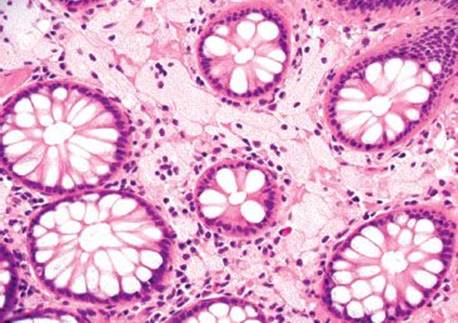

Figure 4.259 PCI. Histologic sections show multiple cyst-like spaces in the muscularis propria.

Figure 4.260 PCI. Alternate image, same patient.

Figure 4.261 PCI. Higher power shows that the cyst-like spaces are lined by histiocytes and foreign body giant cells.

Figure 4.262 PCI. Highest power shows the bland features of the foreign body giant cells lining the empty spaces.